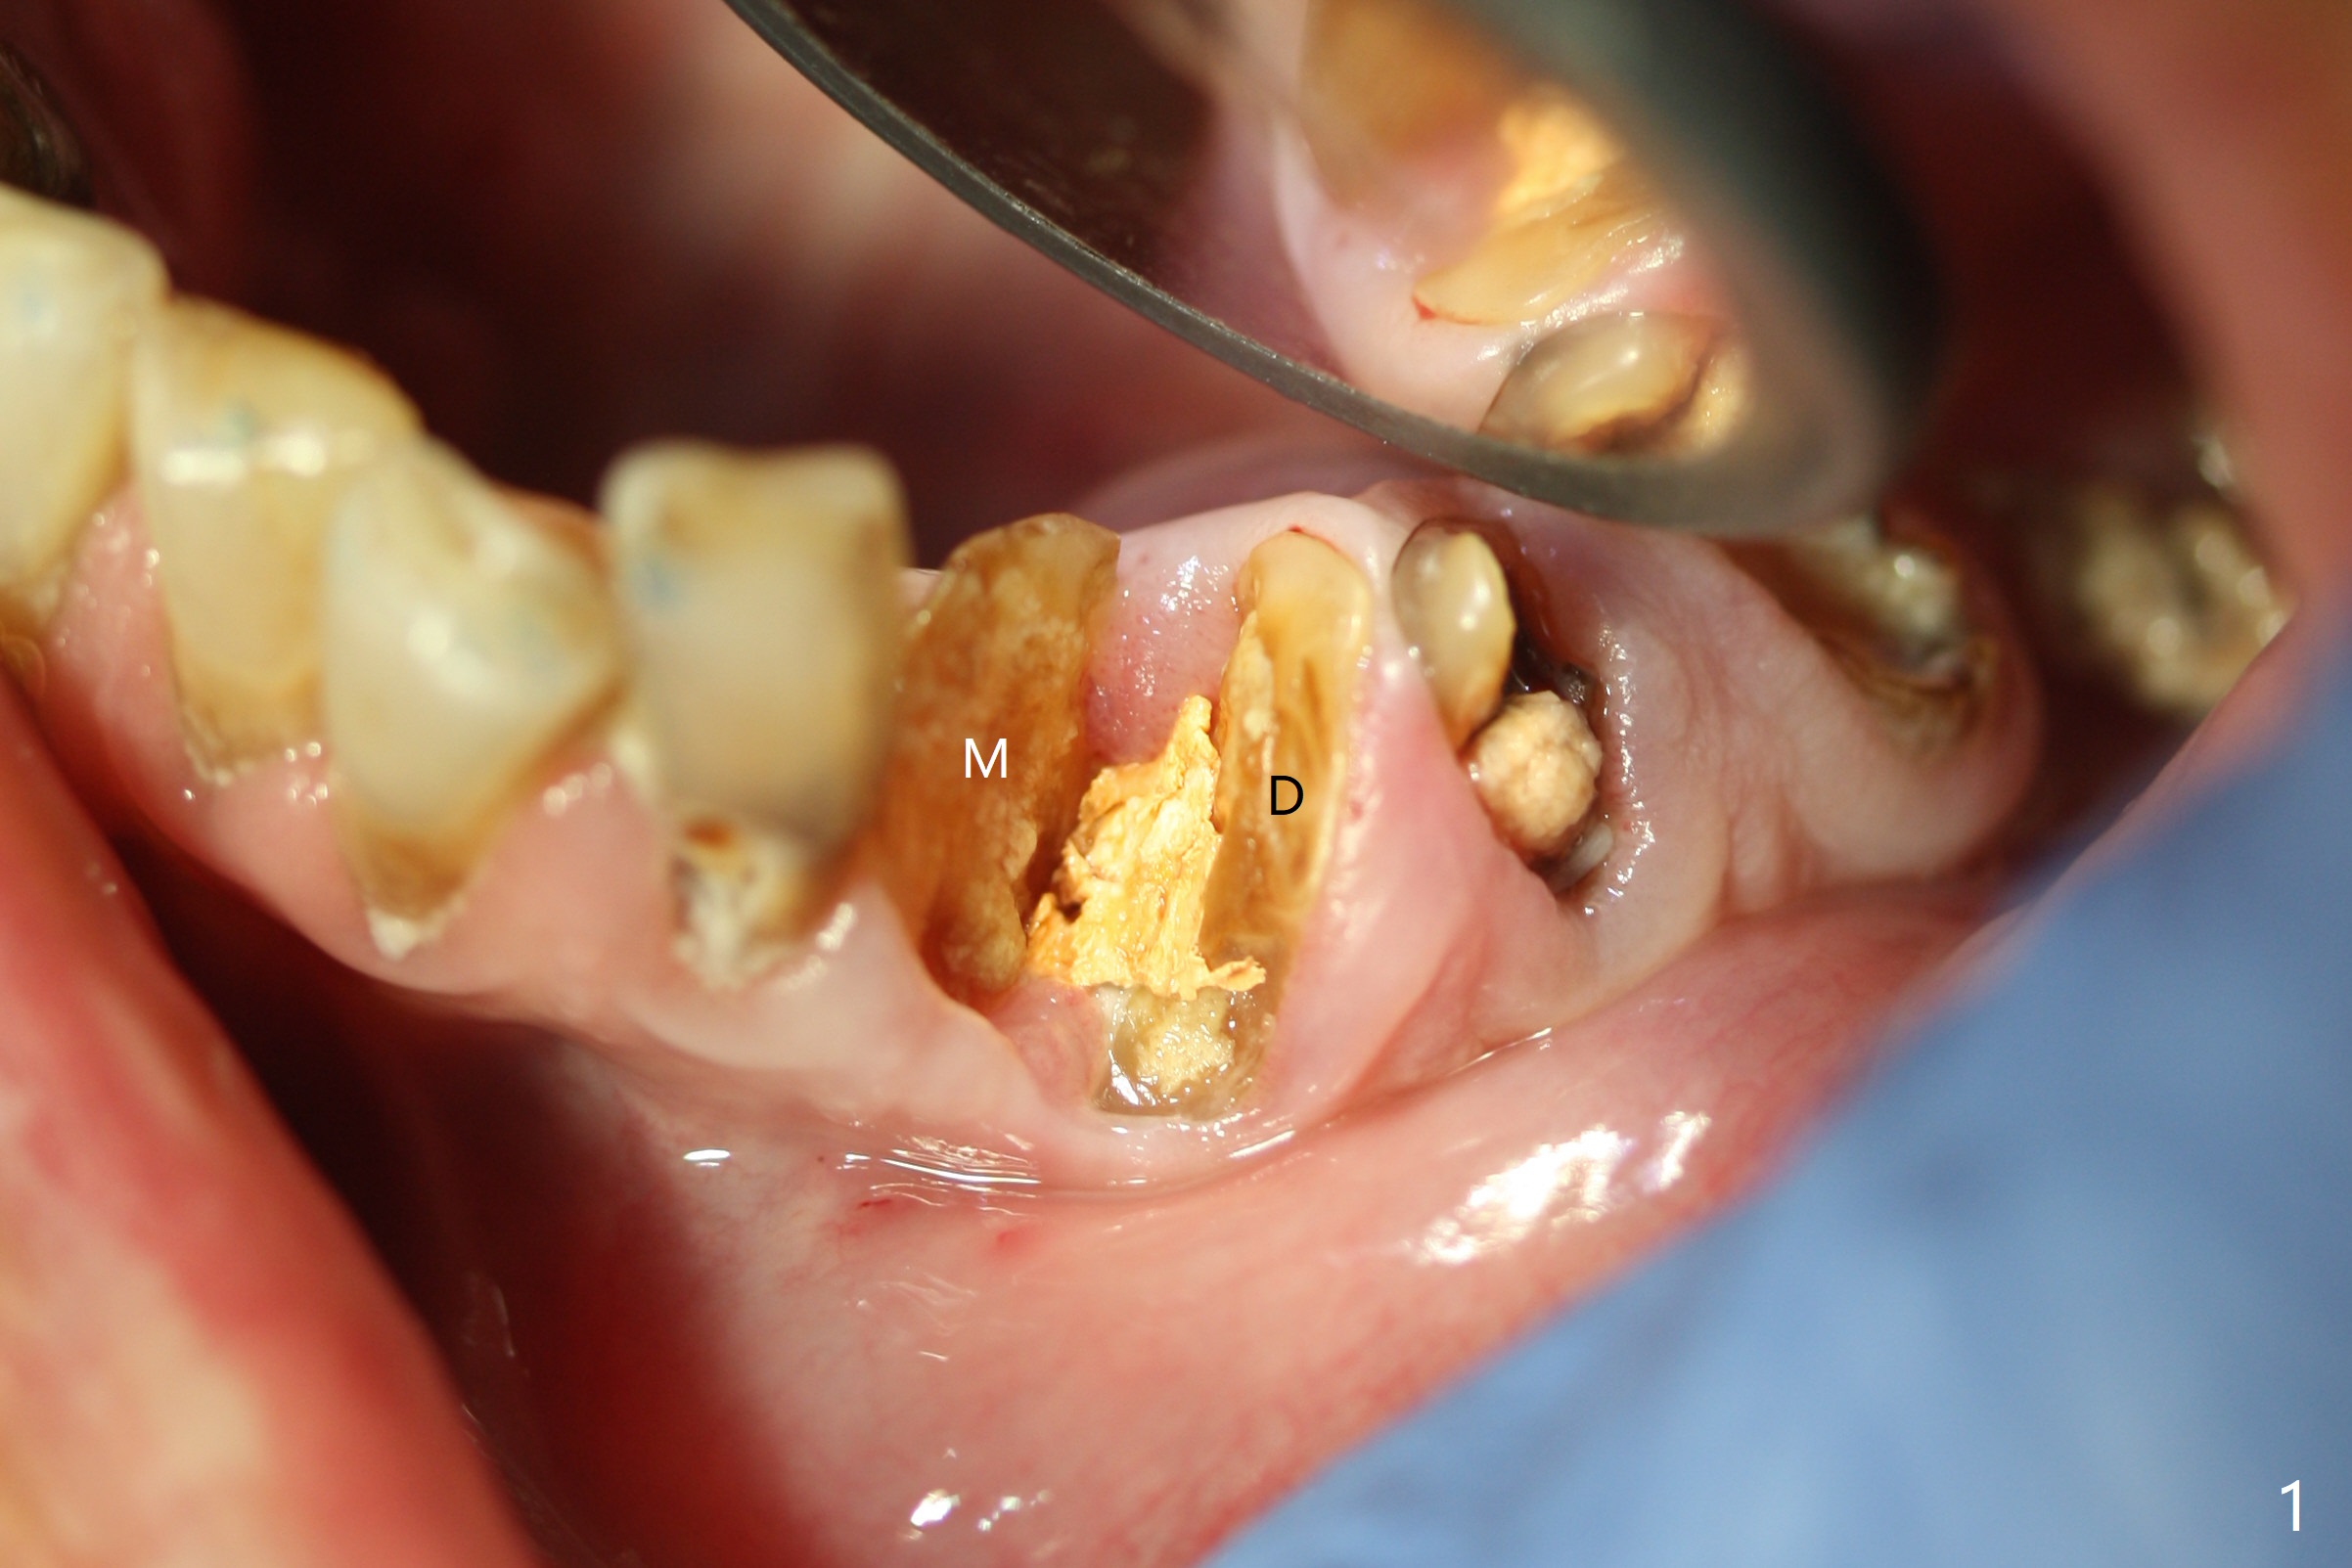

After removal of the split residual roots at #22 (Fig.1), the buccal wall is found to be defective, while the coronal portion of the lingual one (Fig.2 L) is confirmed to be more buccal than the apical portion. A vertical slot is made in the coronal portion of the lingual plate (Fig.3 *) in order to establish osteotomy lingual (Fig.4 O). The depth of the osteotomy in the apical native bone is 4.8 mm (Fig.5 CT coronal section). After the final drill (3 mm) is removed, a 3.8x16 mm implant is placed lingually for secure 2-pointed fixation (Fig.6,7, coronally: mesiolinguodistal; apically: in the native bone (Fig.9)). The essence of the lingual placement is the presence of a large buccal gap for Osteogen plug (Fig.8 yellow) and allograft (Fig.8 red, 9,10 (*)) for potential regeneration of the buccal plate. With bone graft and the overlying provisional (Fig.11 P), the buccal plate seems to have been established (*) 1 week postop. There is no obvious implant thread exposure 8 months postop (Fig.12). But the buccal plate is atrophic when the crown is cemented (~10 months postop, Fig.13).